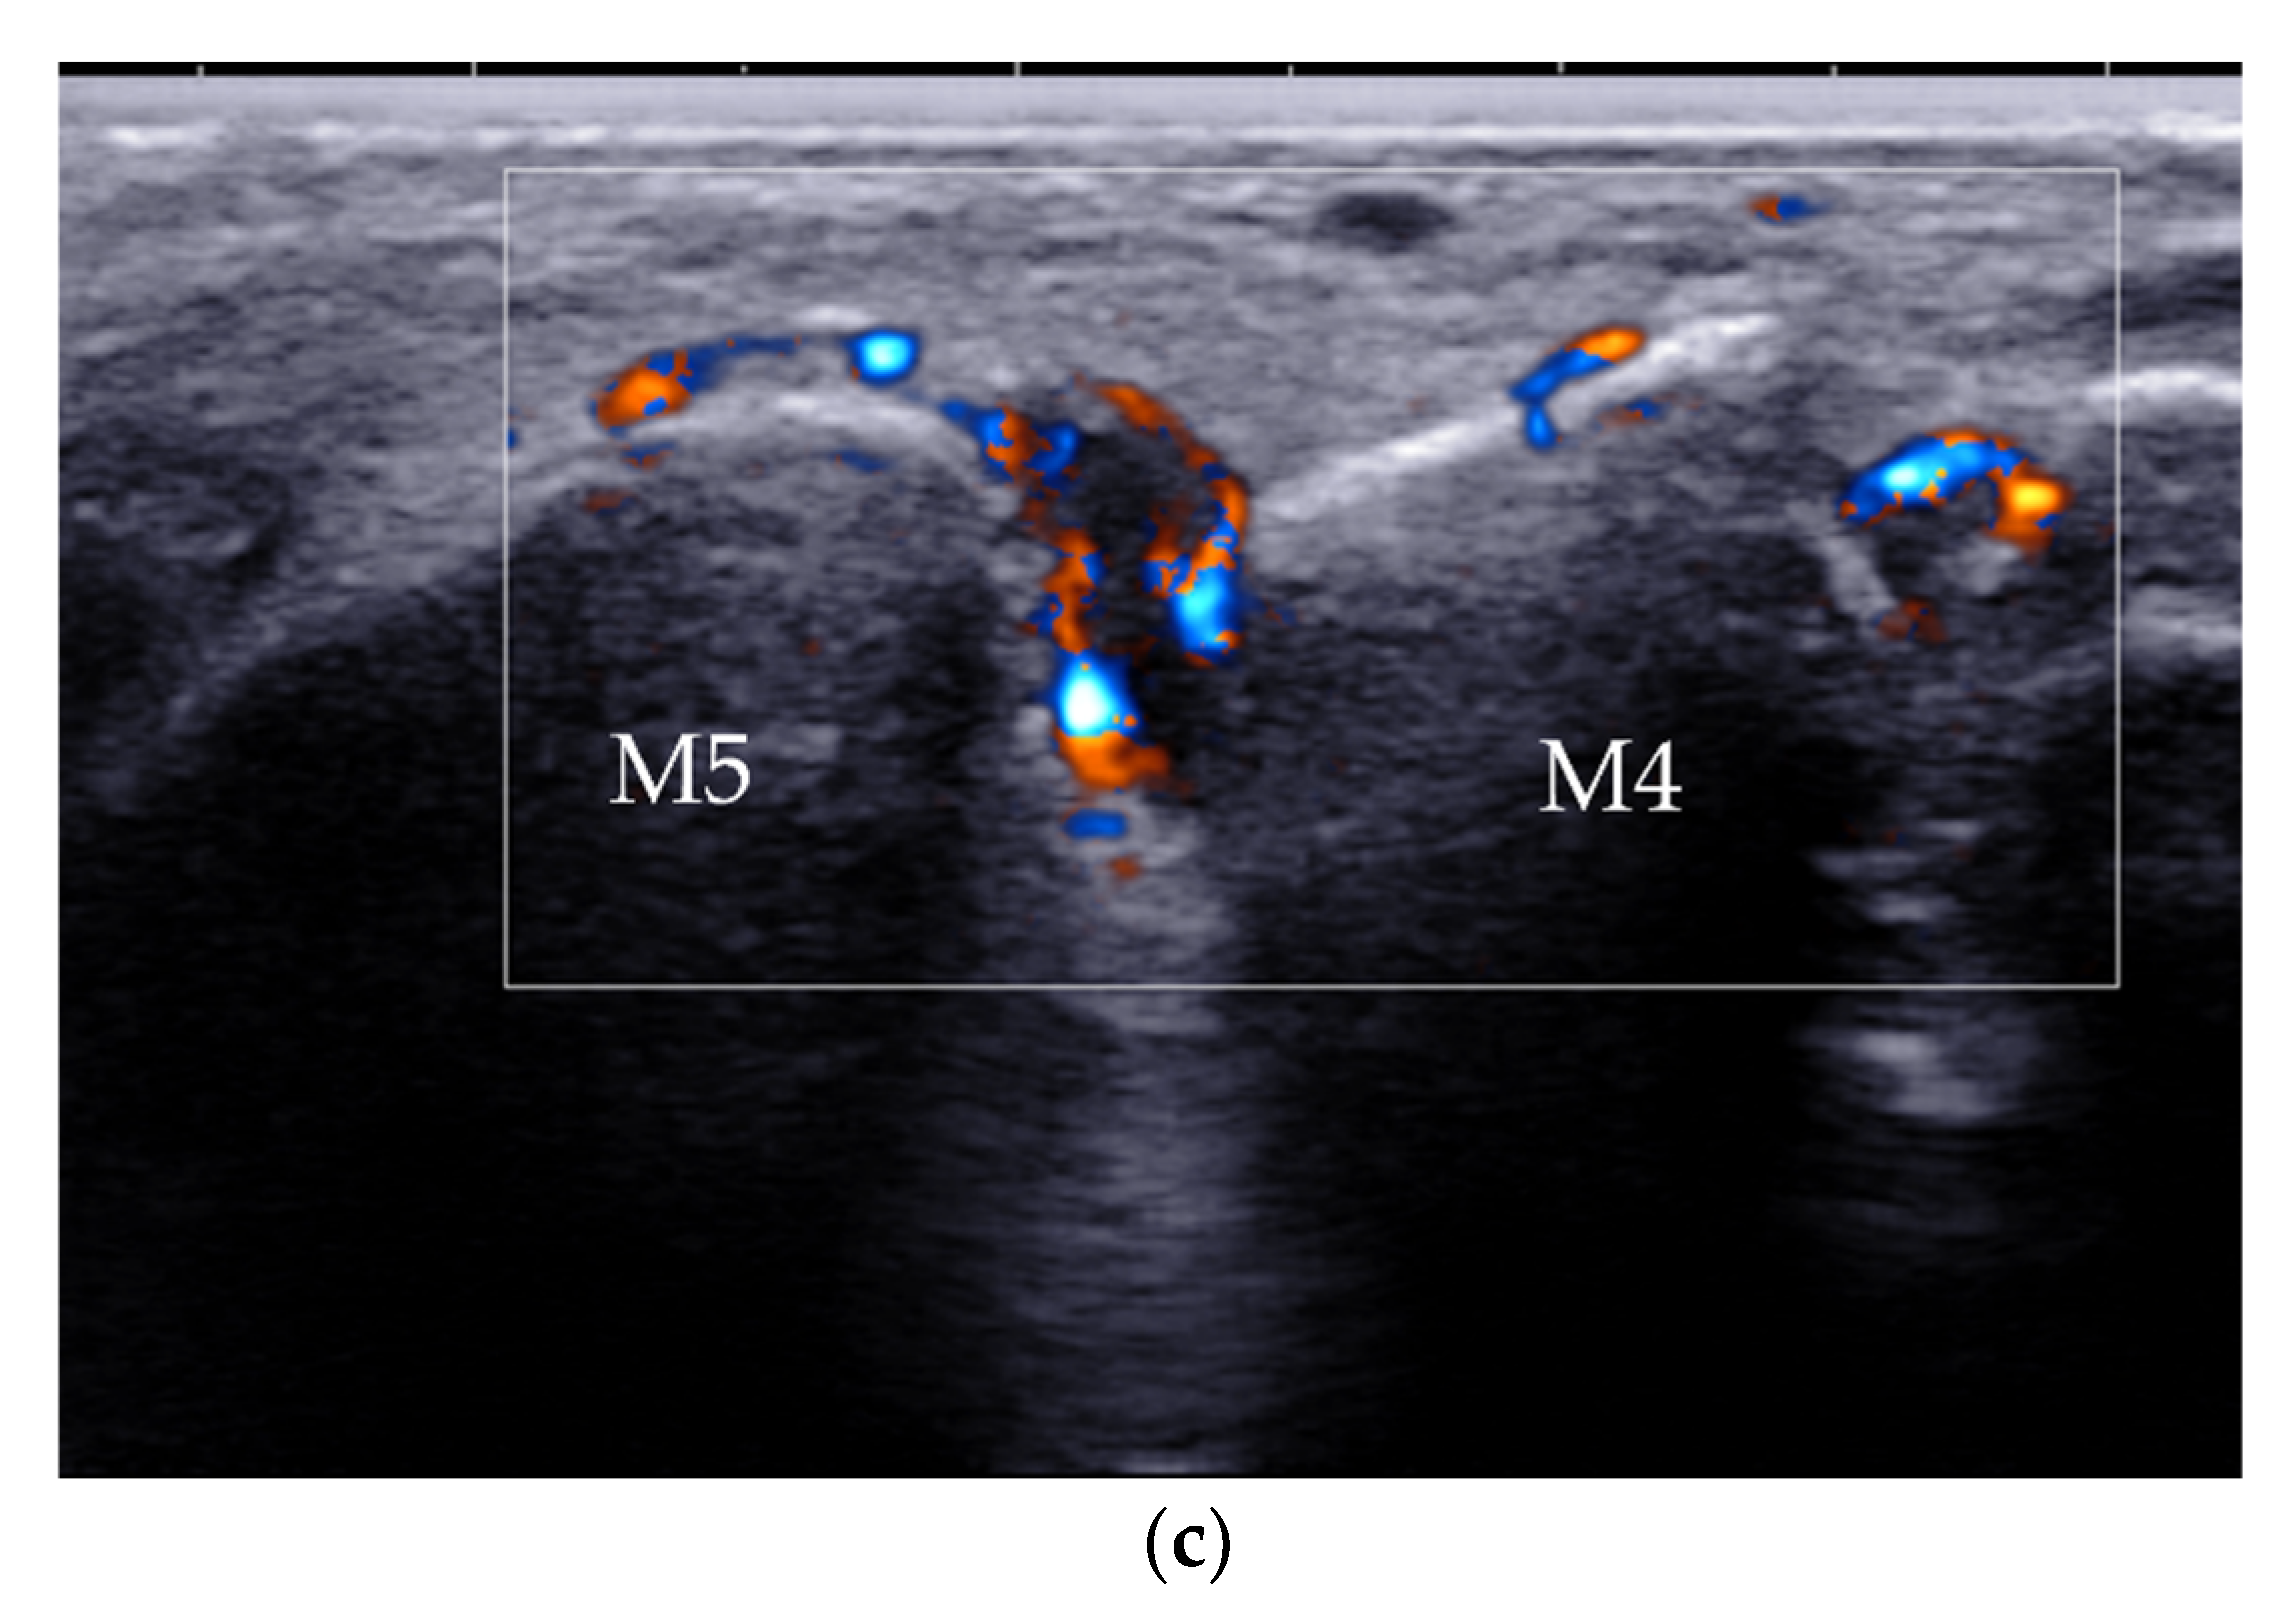

| Intermetatarsal bursitis | intermetatarsal spaces between 2nd and 3rd toes | hypoechoic mass with increased vascularity, compressible |